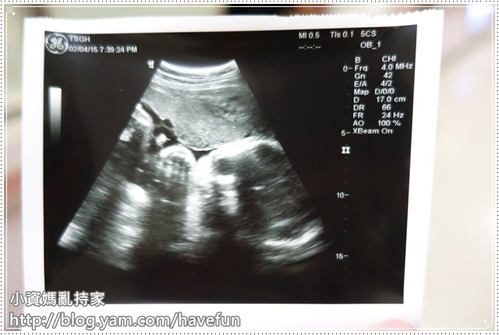

因為是第一次看的醫生,先被叫去照超音波確認孩子狀況

兩個禮拜不見,拉拉又重了兩百多克了